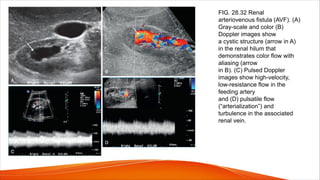

Arteriovenous fistula and arteriovenous malformations

• Renal arteriovenous malformations (AVMs) are abnormal communications

between the intrarenal arterial and venous vessels.

• Renal AVMs are discovered during the workup for gross hematuria.

• Renal AVMs are uncommon; the incidence range is 1 case per 1000 to 2500

patients.

• There are two major types of AVMs: congenital (one-third)and acquired (two-

thirds).

• The acquired type is predominately iatrogenic in origin.

• The term renal arteriovenous malformation usually refers to the congenital

type of malformation.

• Two types of congenital renal AVMs are described: cirsoid (more

common) and cavernous.

• Congenital cirsoid AVMs have a dilated, corkscrew appearance, similar to

a varicose vein.

• Cavernous AVMs have single dilated vessels.

• Acquired renal AVMs are usually termed renal arteriovenous fistulas and

represent as many as 75% to 80% of renal AVMs.

• When the AVF is large, high volume venous flow is observed and is

indicated by elevated Doppler velocity measurements.

• The fistula itself is typically not visualized because the communication is

small, and the affected vessel is obscured by the surrounding bruit artifact.

• The diagnosis can be made by detection of high-velocity, low-resistance

flow within the feeding artery and pulsatile flow within the affected vein

(arterialization of the venous flow)

• Pain, hypertension, and hematuria are typical clinical signs accompanying

the fistula. High-output cardiac failure may occur with large fistulas.

FIG. 28.32 Renal

arteriovenous fistula (AVF). (A)

Gray-scale and color (B)

Doppler images show

a cystic structure (arrow in A)

in the renal hilum that

demonstrates color flow with

aliasing (arrow

in B). (C) Pulsed Doppler

images show high-velocity,

low-resistance flow in the

feeding artery

and (D) pulsatile flow

(“arterialization”) and

turbulence in the associated

renal vein.